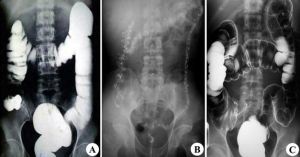

可見多數大致對稱的袋裝凸出,稱為結腸袋,它們之間是由半月皺襞形成不完全間隔。

異常結果:(1)腸腔輪廓改變。惡性腫瘤常邊緣不規則,局部管壁僵硬。息肉境界清楚,邊緣光滑;(2)腸腔大小改變:惡性腫瘤常管腔狹窄局限,炎症所致的狹窄範圍多較廣泛。

1.將鋇劑盛入灌腸筒內,上接導管和消毒肛管,放出少量鋇劑,排除肛管前端少數氣體。將灌筒掛在輸液架上,高度距離台面1M,對比劑溫度和體溫相同。

3.取仰臥位,右側約抬高,在透視下徐徐將鋇劑灌入,當鋇劑通過乙狀結腸進入降結腸而到達脾曲時,則患者左側抬高,有利於鋇劑進橫結腸,結腸肝曲,升結腸,直腸,盲腸。

4.當鋇劑到達升結腸中斷,停止灌注,用體位和手法使盲腸充盈。